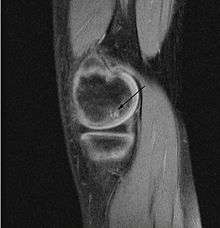

| A large flap lesion in the femur head typical of late stage Osteochondritis dissecans. In this case, the lesion was caused by avascular necrosis of the bone just under the cartilage. | |

Magnetic resonance imaging (MRI) is useful for staging OCD lesions, evaluating the integrity of the joint surface, and distinguishing normal variants of bone formation from OCD by showing bone and cartilage edema in the area of the irregularity. MRI provides information regarding features of the articular cartilage and bone under the cartilage, including edema, fractures, fluid interfaces, articular surface integrity, and fragment displacement.[36][37] A low T1 and high T2 signal at the fragment interface is seen in active lesions. This indicates an unstable lesion or recent microfractures.[29] While MRI and arthroscopy have a close correlation, X-ray films tend to be less inductive of similar MRI results.[37]